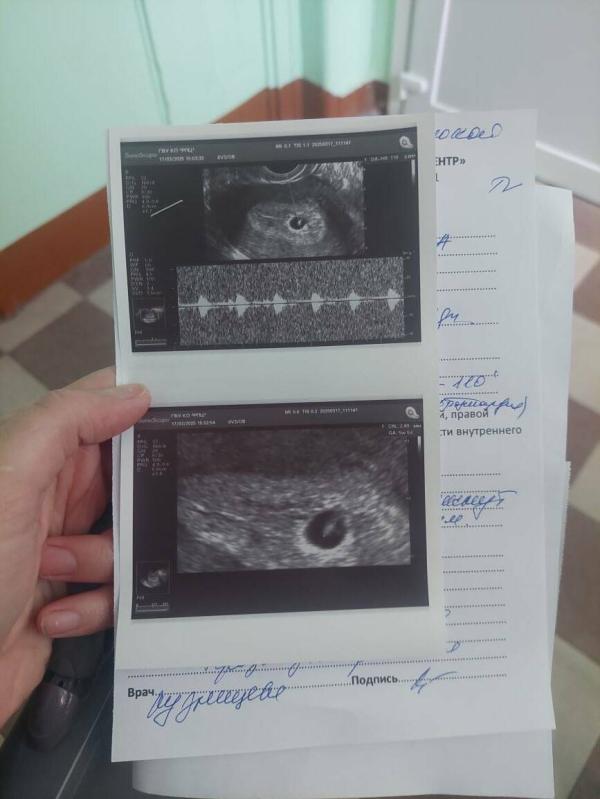

Меня напрягает тот факт что сперва намерили пя размером 15 мм и ктр 3 мм(1 фото) и вроде как по узи предостаточно место